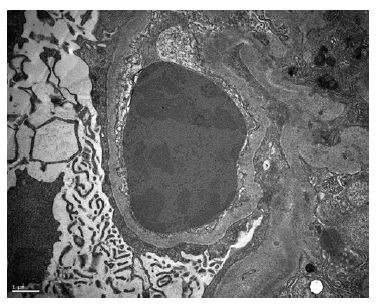

A kidney biopsy was performed, showing on light microscopy 22 glomeruli (Figure 1), one of them with global sclerosis, and five with segmental sclerosis (Figure 2). The remaining glomeruli showed swollen podocytes and segmental mesangial proliferation (Figure 2). Immunofluorescence identified mesangial and granular staining of IgA, C3c, C1q, IgM and IgG. Electron microscopy showed diffuse FPE, with only scant immune deposits confined to the mesangium (Figure 3 and Figure 44).

Figure 1: HE 40x. Kidney biopsy showed tubular necrosis, foci of tubular atrophy and interstitial fibrosis.